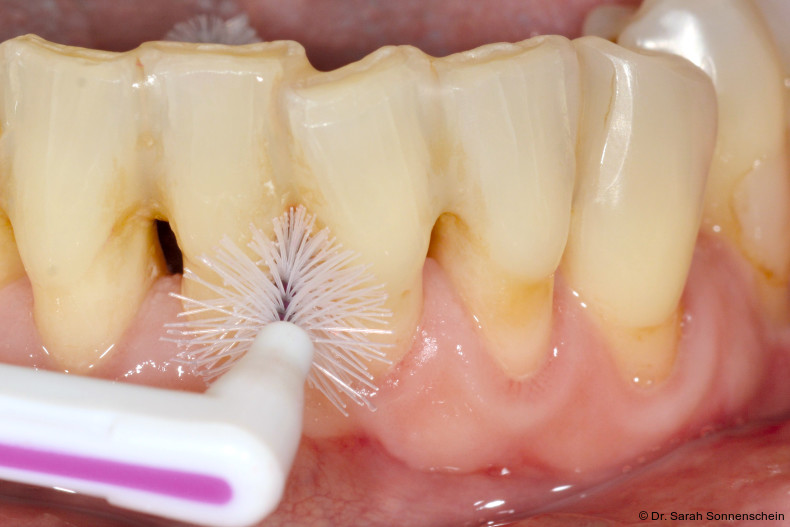

Die im Rahmen eines aktuellen Reviews14 durchgeführte Datensynthese aus zwei retrospektiven Studien zur Schienung parodontal geschädigter und gelockerter Zähne11, 12 kommt zu dem Ergebnis, dass die gewichtete mittlere Inzidenz für Zahnverlust gelockerter und geschienter Zähnen bei 8,4 Prozent innerhalb von zwei Jahren nach nichtchirurgischer Parodontitistherapie lag, wohingegen die gewichtete mittlere Inzidenz für Zahnverlust von den entsprechenden Kontrollzähnen bei 10,1 Prozent lag. In den beiden ins systematische Review eingeschlossenen Studien zeigten die geschienten Zähne im Verlauf der unterstützenden Parodontitistherapie (UPT) stabile parodontale Verhältnisse. Signifikante Veränderungen der Plaquewerte durch die Schienung wurden nicht festgestellt.12 Wird die Schienung aus Stabilitätsgründen über die Schmelz-Zement-Grenze hinaus gestaltet, kann die Konstruktion sogar den positiven Effekt eines Widerlagers für die Interdentalraumbürstchen haben und bei guter Passung die Reinigung für den Patienten einfacher machen. Dies ist besonders bei großen freien Interdentalräumen der Fall. Um den parodontalen Therapierfolg langfristig zu sichern und Karies zu vermeiden, ist nach Einbringen der Schienung eine korrekte Anpassung der Interdentalraumbürstchen für jeden Zwischenraum und die entsprechende Instruktion des Patienten unerlässlich (Abb. 1).

Die Abbildungen 2a–d zeigen die Eingangssituation einer allgemeinmedizinisch gesunden 37-jährigen Nichtraucherin mit Parodontitis Stadium IV Grad C, Falltyp 1 (damalige Diagnose: generalisierte aggressive Parodontitis). Ihr Hauptanliegen war der Zahnerhalt und die Beseitigung der „lockeren“ Zähne. Die Sondierungstiefen lagen generalisiert zwischen 5 und 9 mm. Die AV bei bis zu 12 mm. Die Zähne 33-43 wiesen alle einen Lockerungsgrad III auf. Auch die Oberkieferfront wies einen Lockerungsgrad II auf. Nach der Mundhygienephase erfolgte eine Full-Mouth-Disinfection mit adjuvanter Antibiotikagabe. Die Schienung der Zähne 33-43 erfolgte mittels glasfaserverstärkter Kompositverblockung. Bei Befundevaluation zeigten sich nur noch vereinzelte Taschen von bis zu 5 mm, welche reinstrumentiert wurden. Die Patientin konnte entsprechend in die engmaschige UPT (dreimonatiges Intervall) überführt werden. Zur Verbesserung der Ästhetik und Stabilisierung der gelockerten Oberkieferfrontzähne erfolgte nach Abschluss der aktiven Behandlungsphase ebenfalls eine Verblockung der Oberkieferfrontzähne und Zahnumformung im direkten Verfahren mittels Komposit. Abbildungen 3a–d zeigen die Situation der Patientin zweieinhalb Jahre nach Erstbefundung.